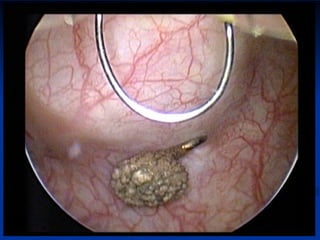

Port Site Recurrence